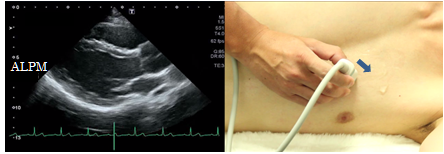

Left ventricular longitudinal view

Parasternal views usually are obtained with the patient in the lateral decubitus position to avoid the effects of air contained in the lungs. To obtain a left ventricular longitudinal view, place the probe on the parasternal area at the 3rd or 4th intercostal space to visualize the left ventricle at the maximum inner diameter and the interventricular septum and the anterior wall of the aorta at almost the same height. This view is suitable for observation of the left ventricle, the right ventricle, the mitral valve, the aortic valve, and the proximal part from the Valsalva sinus to the ascending aorta.